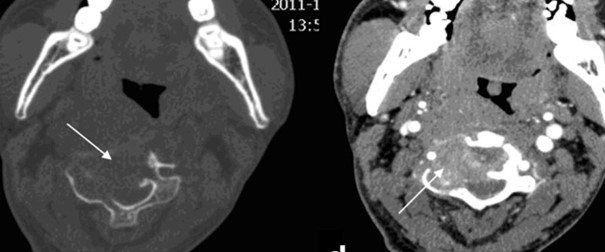

• CT

• 左:CT(骨条件)、右:造影CT